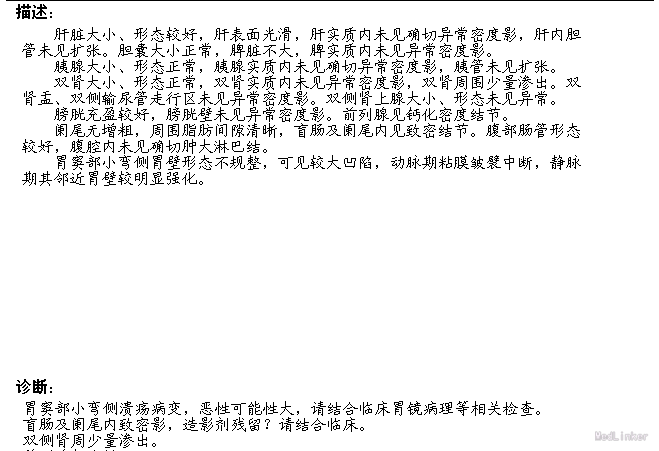

查体:体温36.5℃,呼吸:18次/分,心率89次/分,血压115/79mmHg。神清语明,步入病房,查体合作。贫血貌,周身皮肤及粘膜无黄染及出血点,浅表淋巴结未触及肿大,颈静脉无充盈。巩膜无黄染,睑结膜苍白,口唇无发绀。双肺听诊呼吸音清,双肺未闻及明显干湿罗音。心音低钝,律齐,听诊心率66次/分,各瓣膜听诊区未闻及病理性杂音。腹部无压痛,无反跳痛及肌紧张,肝脾肋下未触及,无肝肾区叩击痛。双下肢无水肿。 辅助检查:腹部增强CT:胃窦部小弯侧溃疡病变,恶性可能性大。

诊断:胃癌;中度贫血;冠心病陈旧性心肌梗死;高血压2级(极高危);冠脉造影及支架植入术后 治疗:全麻下行胃癌根治切除(D2)、Billorth-I式吻合、空肠营养造瘘术,手术顺利,术后恢复可,术后第7天,患者突然出现右侧腹部疼痛,后转移至下腹及左侧髂腹部等,吻合口后引流管引流出暗黄色浑浊液体,留置胃管后引流出同性质液体,考虑吻合口瘘,复查全腹CT平扫,肝周积液较前增多。请介入科行肝周积液的穿刺引流,同时经空肠营养管予肠内营养,但患者仍持续高热,经介入科第二次穿刺引流后,患者体温由39.5℃逐渐下降至正常。